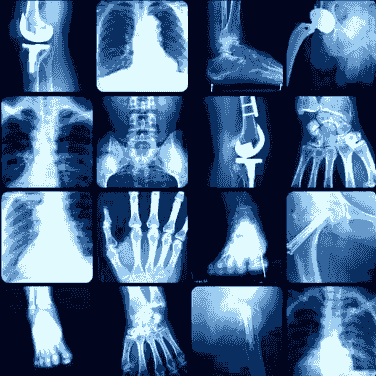

基於症狀的護理/管理

過程包括諮詢、調查、檢查和診斷測試(X光、MRI、CT...等),以找出脊椎相關症狀的根本原因,並提供診斷資訊及提供治療,以消除任何有機會可減慢身體恢復時的阻礙,治療主要集中在脊椎矯正調整、肌肉和生物力學(肌肉耐力)等基礎上的緩解,並使用必要的機器來緩解診斷症狀,我們可以接受同時不會惡化的症狀並恢復到正常狀態盡快恢復正常生活。當我們控制症狀時,將建議需在最後階段做好一定的保健,以主動預防症狀再次出現(醫生、護理師和患者),例如:定期調整、復健、吸取營養補充品、簡單的拉根或運動等......

所在時區:亞洲/香港 GMT+08:00立刻預約X-Ray (X光影像) 或 MRI (磁力共振影像)

X-Ray (X光影像) 或 MRI (磁力共振影像) 轉介到影像中心選擇日期與時間

X光影像檢查

(一個部位

"例如:頸椎")

X-Ray Imaging

(1part of the body)

HKD$750